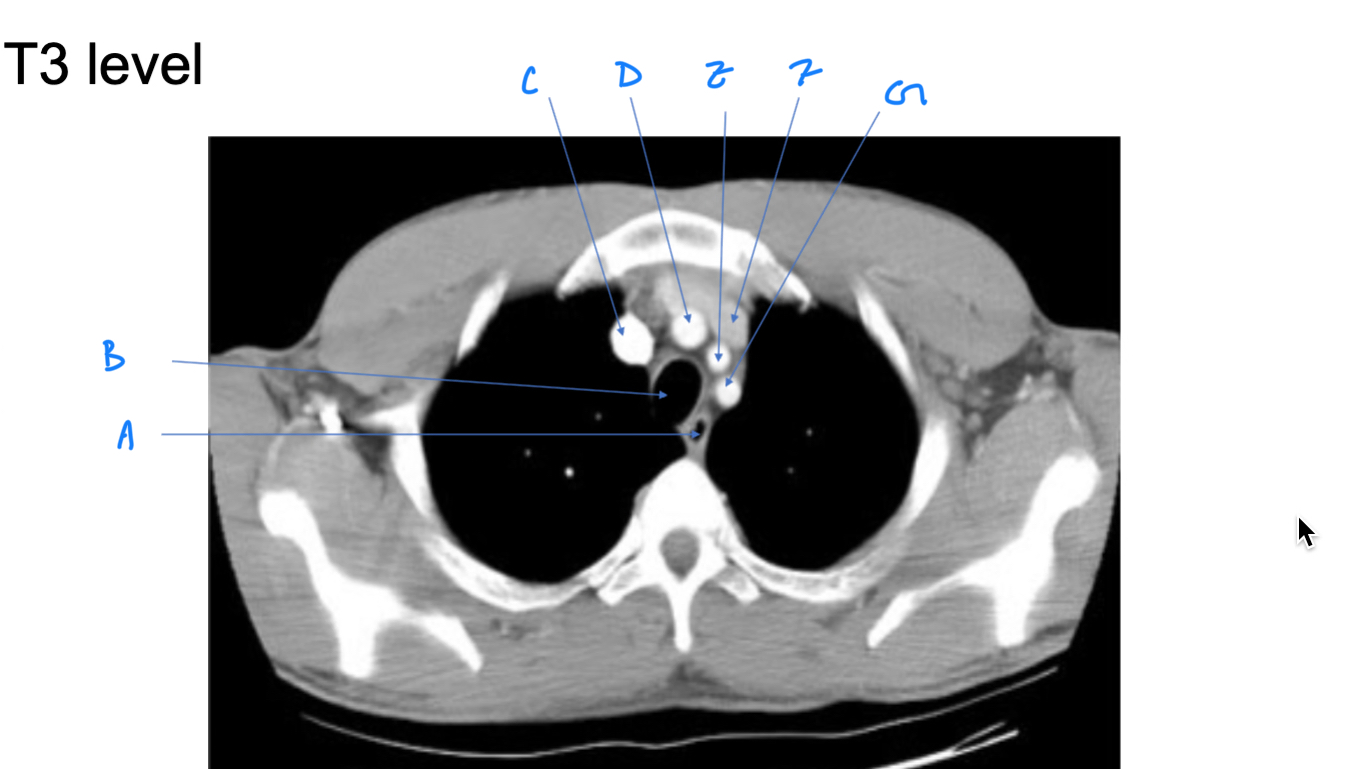

Esophagus

A. Identify

Trachea

B. Identify

R Brachiocephalic v.

C. Identify

Brachiocephalic trunk

D. Identify

L CCA

E. Identify

L Brachiocephalic v.

F. Identify

L Subclavian a.

G. Identify

Trachea

A. Identify

Superior vena cava (SVC)

B. Identify

Arch of aorta

C. Identify

Esophagus

D. Identify